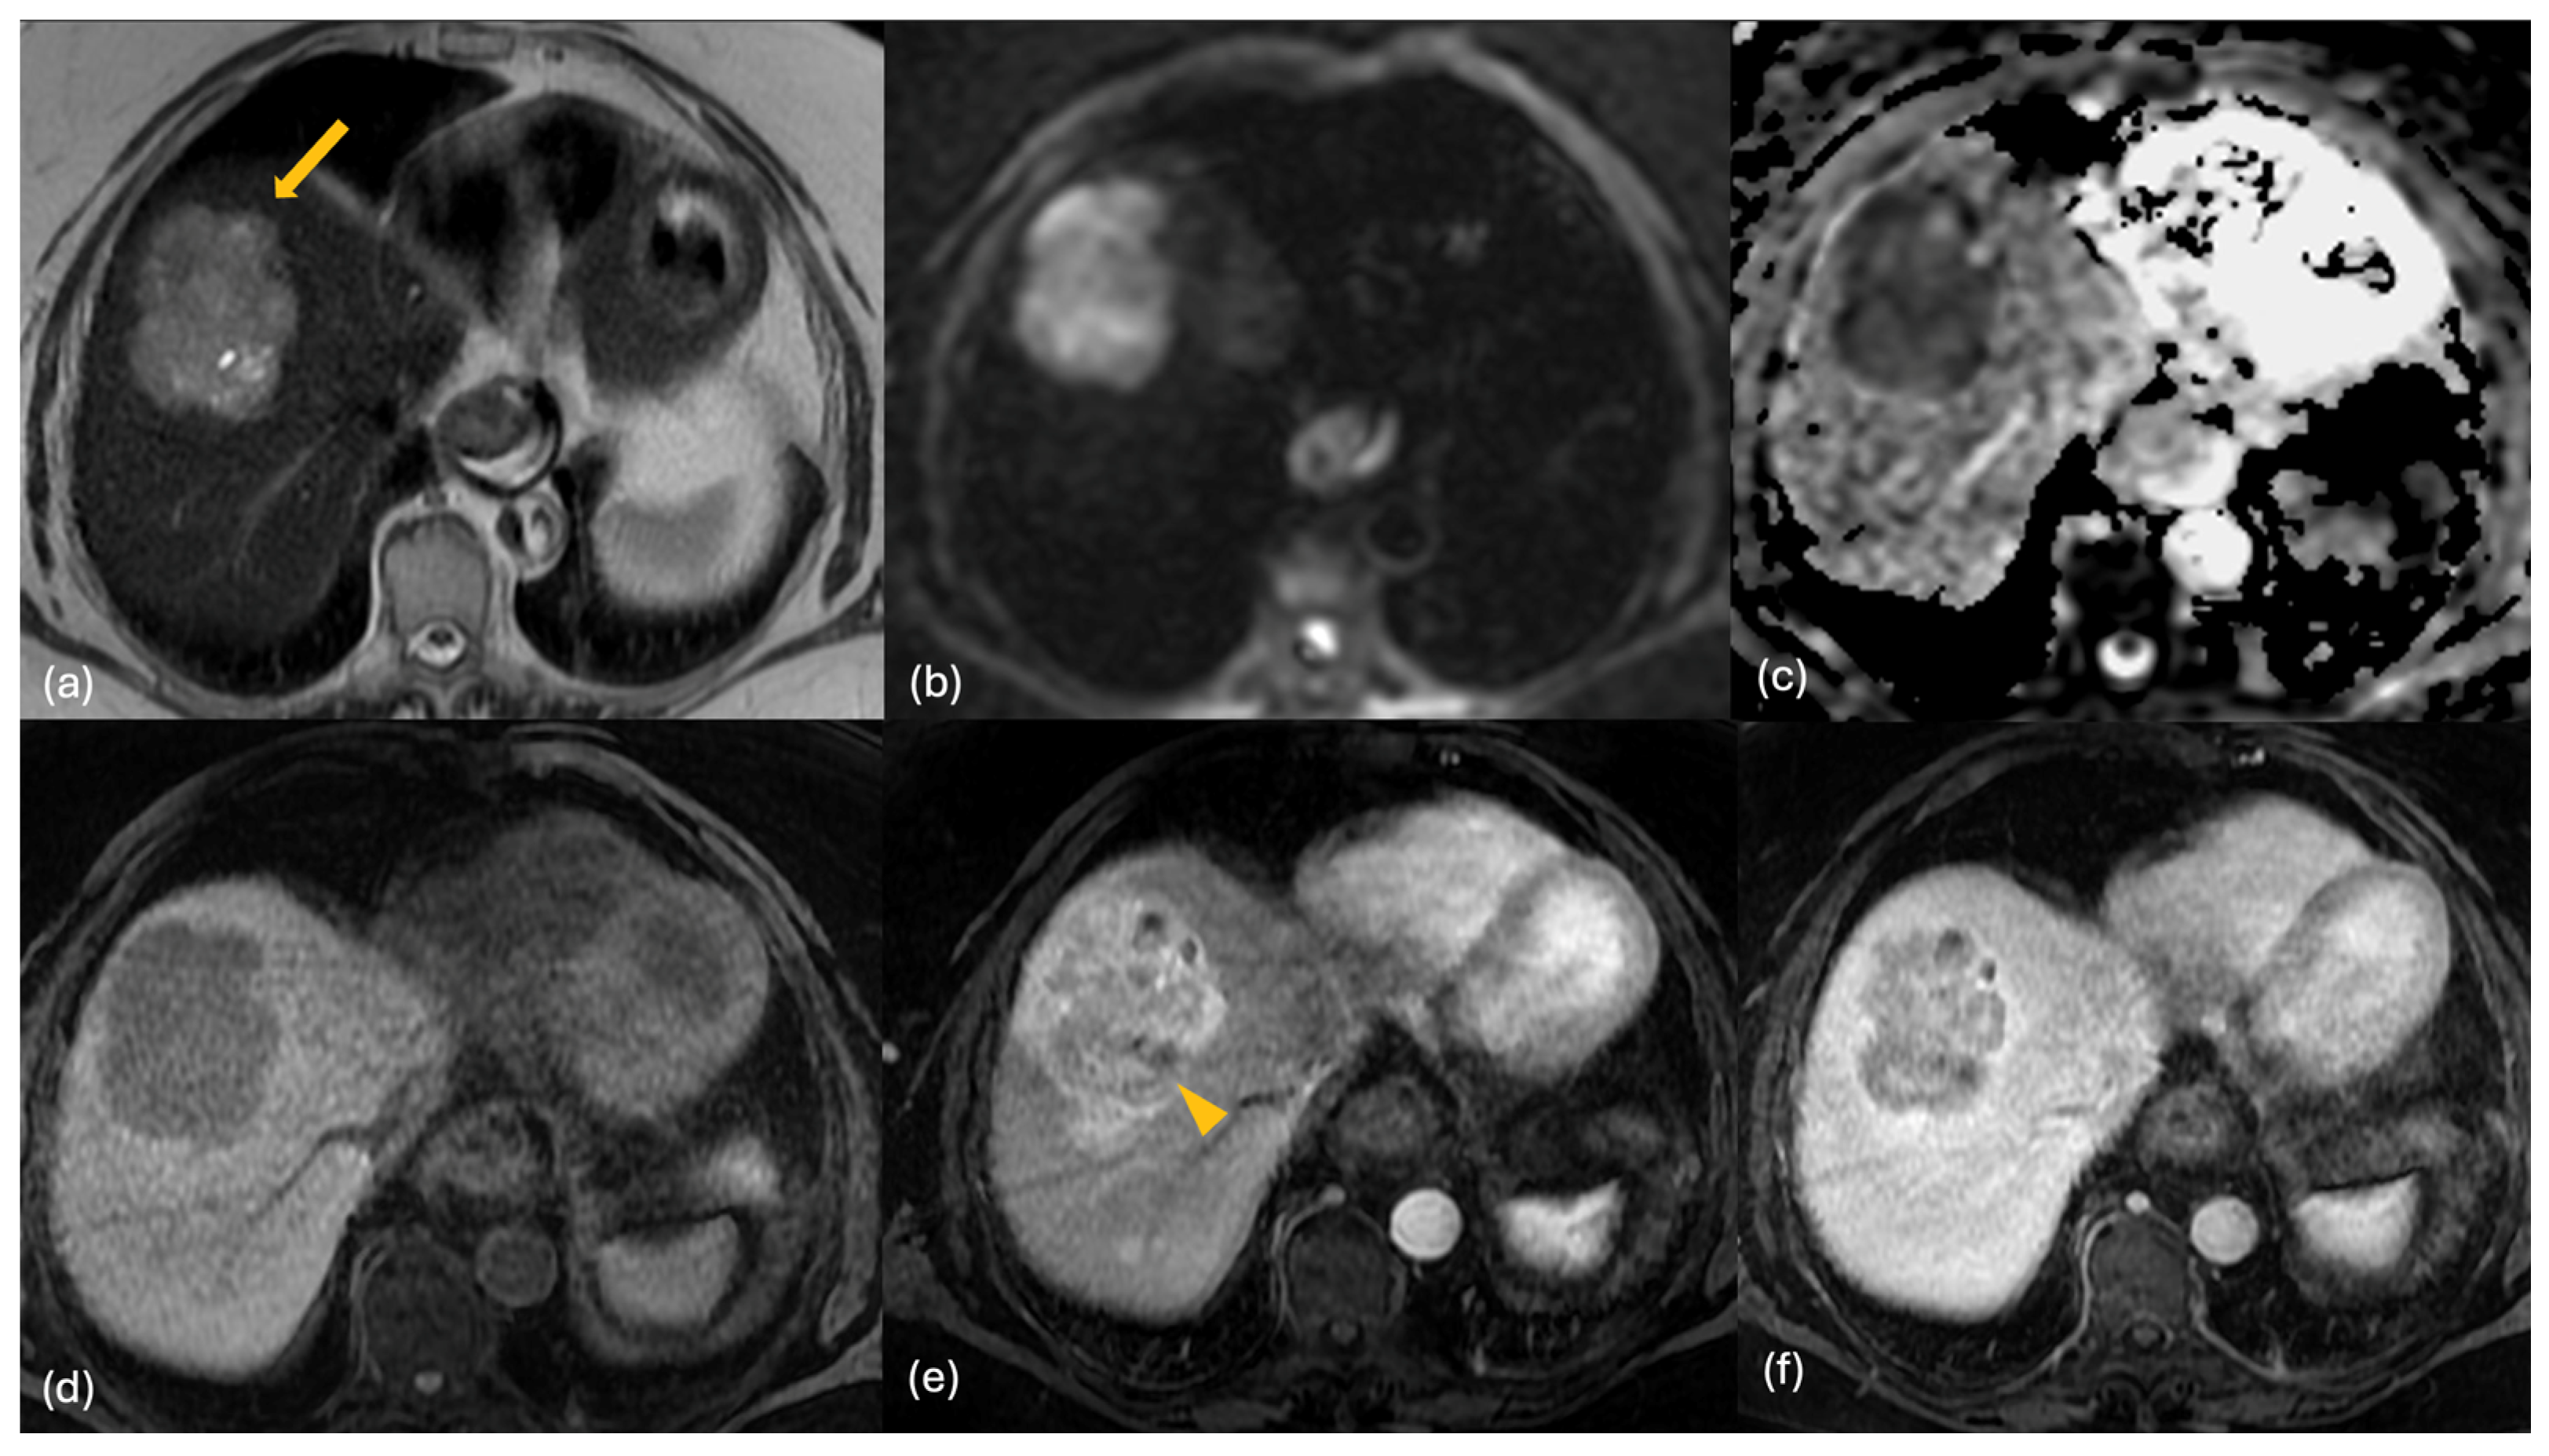

2.3. MRI